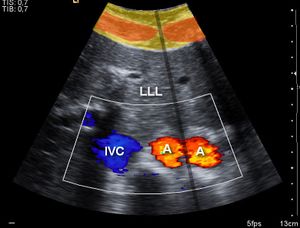

Hemodynamics (blood circulation)

Blood velocity can be measured in various blood vessels, such as middle cerebral artery or descending aorta, by relatively inexpensive and low risk ultrasound Doppler probes attached to portable monitors[3]. These provides non-invasive or transcutaneous (non-piecing) minimal invasive blood flow assessment. Common examples are, Transcranial Doppler, Esophogeal Doppler and Suprasternal Doppler.